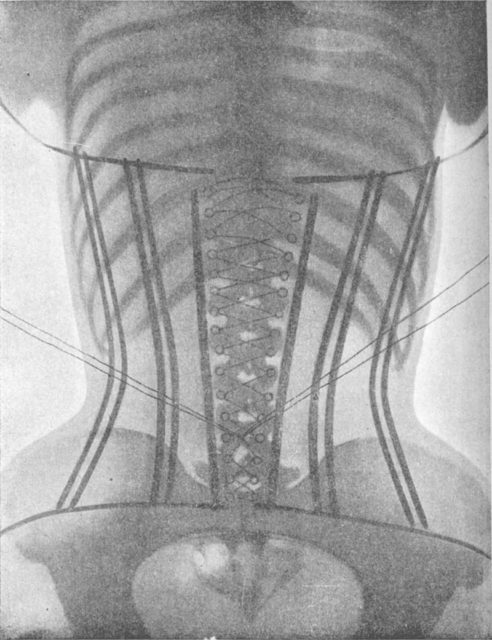

1. Corset

No woman in the world will tell you that she doesn’t want to have a slim waist. However, having a tiny waist is not a new fashion trend.

Considered by many to be one of the most dangerous fashion trends, the corset restricted women’s breathing which often led to fainting. However, fainting wasn’t the worse thing that could happen to a woman trying to keep pace with fashion at the time.

Internal organs were also subject to damage as they were forced to shift from their natural position and this could eventually lead to internal bleeding. Broken ribs, digestive problems, hysteria, melancholy, and constipation are just a microscopic part of nearly 100 diseases attributed to corset wearing.